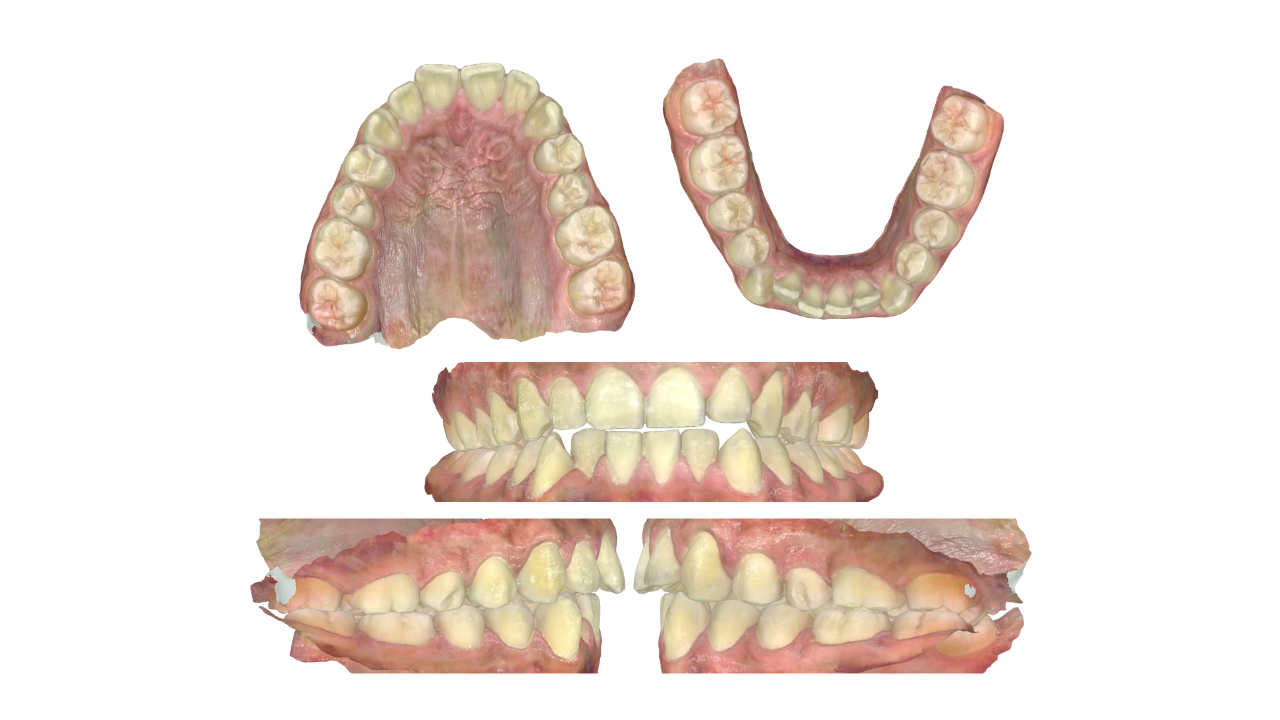

C A S E 1

Class 1: Upper spacing, lower mild crowding

Plan: Non-extraction, U+L fixed appliances, retain